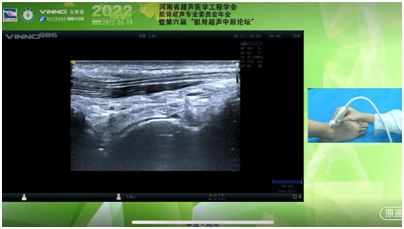

国内知名的肌骨超声专家朱家安教授、崔立刚教授、邱逦教授、张华斌教授分别就肌骨超声在神经、关节、风湿免疫类疾病及肌肉的最新进展和应用进行了专题讲座;来自省内的超声专家沈素红教授、张煜华教授、刘博教授、郭晓霞教授、段少博教授参与主持会议并进行讨论;河南省洛阳正骨医院河南省骨科医院郑州院区的席占国教授携七位年轻专家进行了病例分享以及全身 六大关节的肌骨超声操作演示、病例演示;河南省洛阳正骨医院(河南省骨科医院)郑州院区功能检查科主任、河南省超声医学工程学会肌骨专委会主任委员席占国做总结发言;十万余名全国各地的超声同道线上观看了会议并进行了热烈讨论。